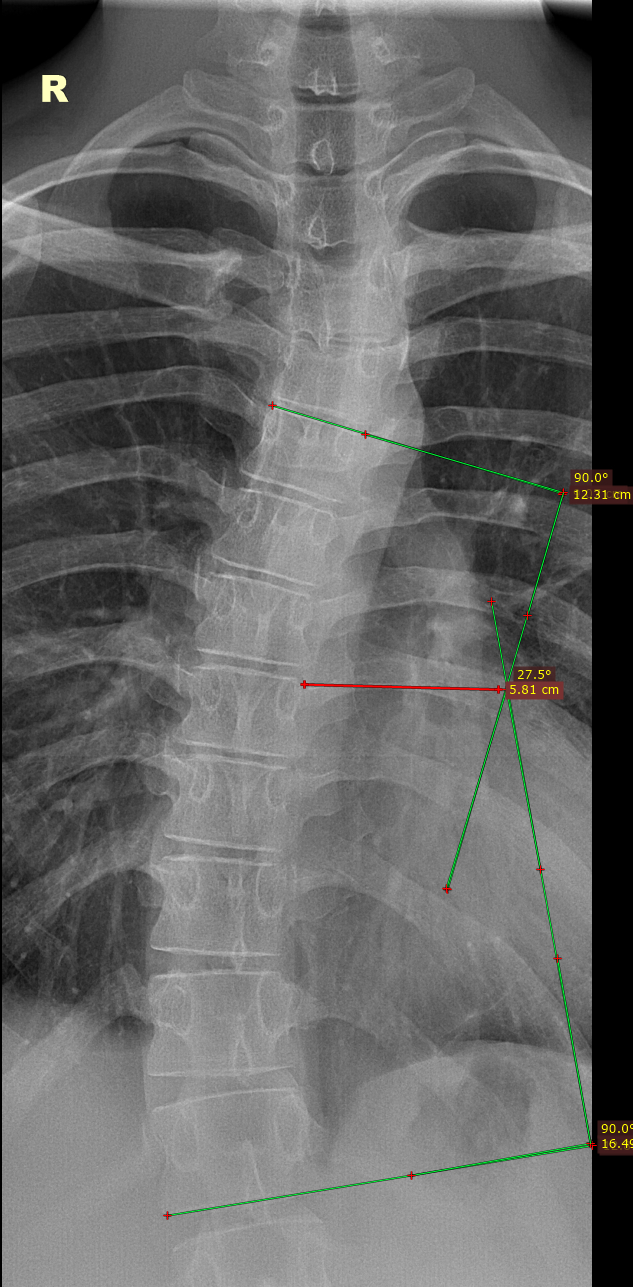

При укорочении нижней конечности,X и O-образных деформациях нижних конечностей, нужно направлять призывников на панорамную рентгенографию нижних конечностей(это современный метод, который позволяет получить единое рентгеновское изображение всей длины обеих ног, от костей таза до стоп. Для этого используются современные аппараты, которые автоматически «сшивают» серию снимков в одно цельное изображение), но такая аппаратная возможность есть не во всех мед. учреждениях.

Также, для подтверждения укорочения нижней конечности используется тест для определения истинной длины нижней конечности. Чтобы точно измерить длину нижней конечности, необходимо, чтобы пациент лежал на плоской твердой поверхности. Обе ноги должны находиться в одинаковом положении. Измерение производится от передней верхней ости подвздошной кости до дистальной медиальной лодыжки на той же стороне. Затем сравниваются данные, полученные с обеих сторон.

У выше представленного призывника, при измерении истинной длины нижних конечностей, выявлено укорочение правой нижней конечности на 2.5 см., что соответствует ст.69в-В(ограниченно годен к в/сл)